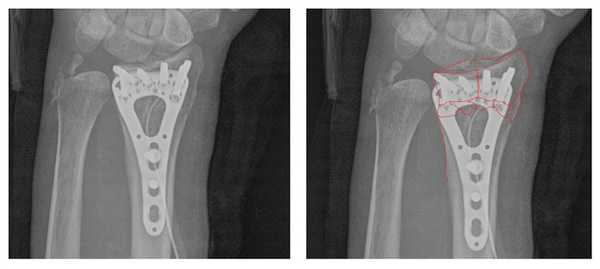

Например у Пациентки А, 24 лет, операция выполнена по поводу относительно простого перелома дистального метаэпифиза лучевой кости с угловым смещением к тылу на 30 градусов и укорочением лучевой кости на 7 мм. Учитывая молодой возраст и высокие функциональные запросы принято решение о выполнении остеосинтеза. Учитывая сохранность волярного кортекса использована пластина меньшего размера, которая установлена более проксимально, с целью максимального сохранения кровоснабжения эпифиза лучевой кости.

Через 6 недель наблюдается рентгенологическое сращение перелома. Функция конечности к этому времени уже практически полностью восстановлена.

В случае дистальных переломов, расположенных ближе к лучезапястному суставу, может возникнуть необходимость расположить пластинку ближе к суставной поверхности. Для этого лучше использовать специальную пластинку VA-LCP™ Volar Rim Distal Radius Plate.

Клинический пример. Пациентка С. 36 лет, травма при падении во время матча по большому тенису, получила закрытый оскольчатый перелом дистального метаэпифиза лучевой кости с большим количеством мелких фрагментов в метафизарной зоне.

На 7 сутки после получения травмы пациентка обратилась в Клинику К+31, учитывая нестабильный характер перелома предложено оперативное вмешательство. Для остеосинтеза использована пластина VA-LCP™ Volar Rim Distal Radius Plate.